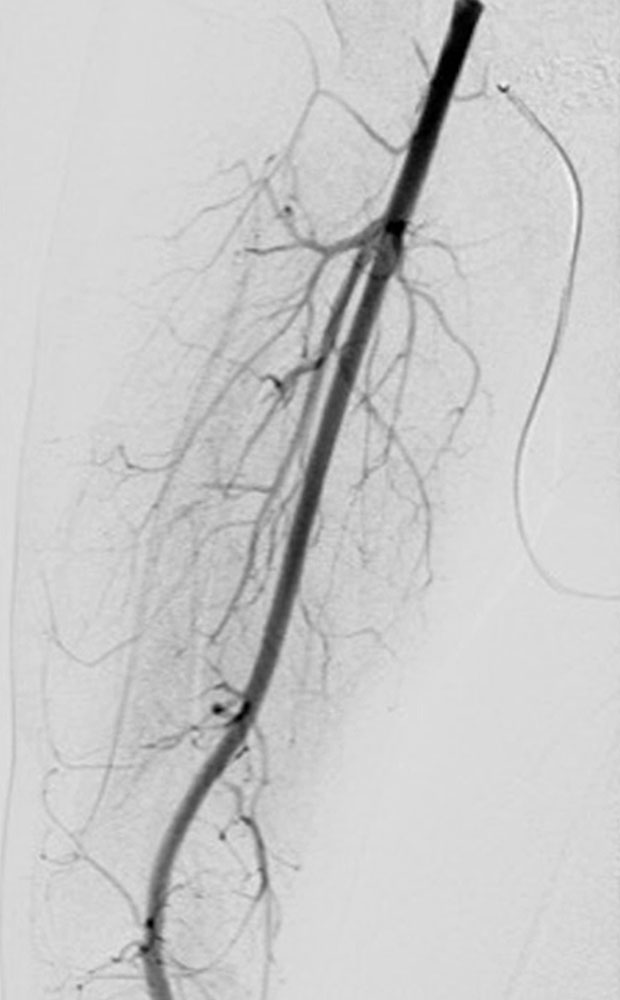

• Embolization of arteriovenous fistulas (in the case of complications or locally before epiphysiodesis)

Microfistulous AVM/AVF can be found not only in the subcutis but also in the muscles and bones.

Parkes Weber syndrome (PWS) is characterized by the combination of cutaneous capillary malformations (CM) and arteriovenous malformations (AVM) and multiple very fine arteriovenous fistulas (AVF) with an ipsilateral circumscribed overgrowth of an extremity. Lymphatic malformations (LM) may also be present and appear as lymphedema.